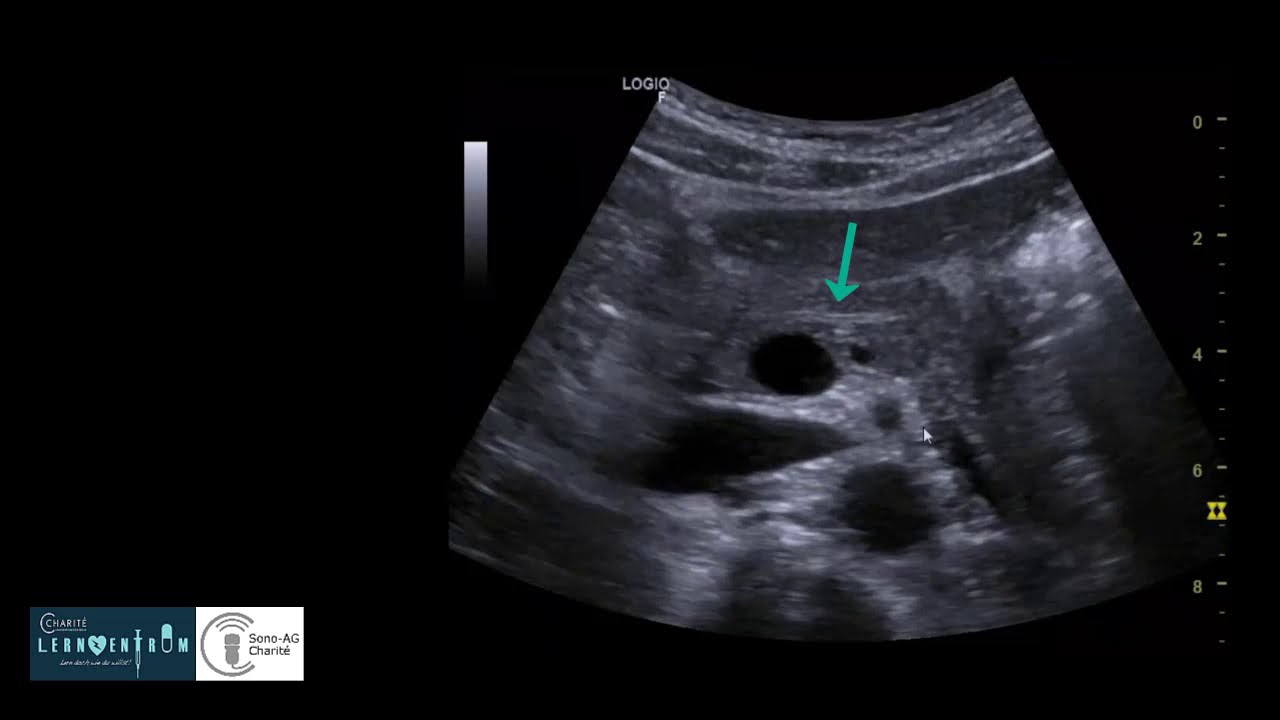

3D Lehrvideo: Ultraschalluntersuchung des weiblichen Beckens - SonoSite Ultraschall

Mit dem Einsatz von 3D animierten Videos können wir Ihnen nun in neuer Darstellung zeigen, wie portable Ultraschalluntersuchungen durchgeführt werden. In diesem Lehrvideo sehen Sie die Vorführung einer Ultraschalluntersuchung des weiblichen Beckens.

Anleitung: Intrauterine Schwangerschaft – Teil 1